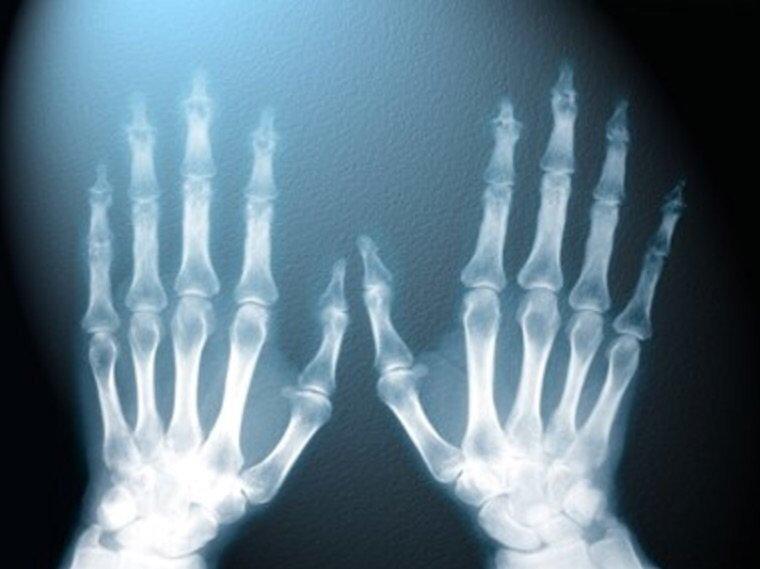

Если задуматься, все виды излучения способны проникать в ткани. Но именно рентгеновское излучение дало возможность использовать это свойство на практике в медицине.

Если сравнить лучи рентгеновского происхождения с лучами света, то первые имеют очень большую длину, что позволяет им проникать даже через непрозрачные материалы. Такие лучи не способны отражаться и преломляться. Данный вид спектра имеет мягкую и жесткую составляющую. Мягкая состоит из длинных волн, способных полностью поглощаться тканями человека. Таким образом, постоянное воздействие длинных волн приводит к повреждению клеток и мутации ДНК.

Есть ряд структур, которые не способны пропустить через себя рентгеновские лучи. К ним относится, например, костная ткань и металлы. Исходя из этого и производятся снимки костей человека с целью диагностики их целостности.

В настоящее время созданы приборы, позволяющие не только делать фиксированный снимок, например, конечности, но и наблюдать за происходящими с ней изменениями «онлайн». Эти устройства помогаю врачу выполнить оперативное вмешательство на костях под контролем зрения, не производя широких травматичных разрезов. При помощи таких приборов можно исследовать биомеханику суставов.